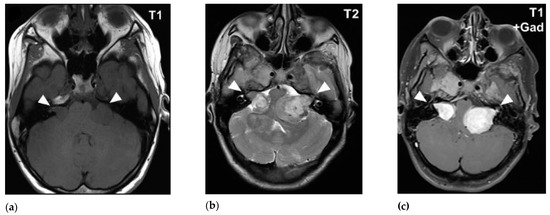

MRI is the standard imaging technique to assess the size, aspect, location and the evolution of VS. The ‘gold standard’ for diagnosing VS is the gadolinium-enhanced T1-weighted MRI sequence. Volume analysis using MRI imaging is preferred to evaluate the change in tumor size. A change of 20% in volume is considered clinically significant. Sometimes this can result in false-positive findings mainly with small lesion-like abnormalities [49,50]. T2-weighted MRI can help to show peritumoral oedema and the presence of cysts [51,52]. There are no major differences in MRI characteristics with routine imaging between NF2 VS and sporadic VS (Figure 1 and Figure 2).

Figure 1. MRI imaging of sporadic vestibular schwannoma (VS) in cerebellopontine angle: (a) T2-weighted MRI reveals sporadic VS as hypointense signals and (b) T1-weighted image with contrast demonstrates hyperintensity of sporadic VS (courtesy of Y. Temel).

Figure 2. MRI imaging of bilateral NF2 VS in cerebellopontine angle: (a) T1-weighted MRI reveals bilateral NF2 VS as hypo-intense signals; (b) T2-weighted MRI and (c) T1-weighted MRI with contrast demonstrates hyperintensity of bilateral NF2 VS [53].

VS are hypo- to isointense or isointense when compared to brain parenchyma on T1-weighted images [54,55,56]. Tumoral cysts are hypointense in comparison to the brain parenchyma on T1-weighted images [54,57]. The T1-weighted images can visualize intratumoral hemorrhage as an isointense or hyperintense area [58,59]. On T2-weighted images VS shows hyperintense signals [55,60]. The cysts of VS are hyperintense and the tumor can appear heterogeneous when there is cystic degeneration [58,61]. Hemorrhage can be seen as a hypointense signal on T2-weighted images [58]. Intratumoral hemorrhage can occur in VS due to its high vascularity [1,62]. Since T2-weighted imaging has high resolution and lower costs it can be used as the follow-up modality [63].